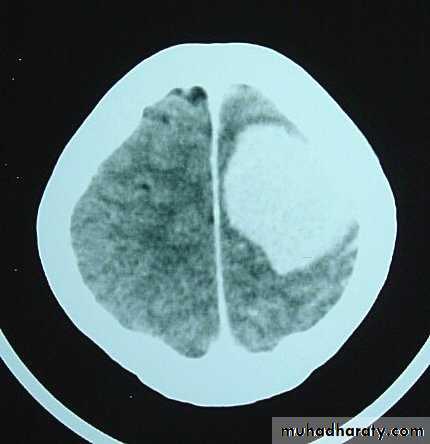

Metastatic Brain Tumours Pre contrast CT

Metastatic Brain Tumours Post contrast CT